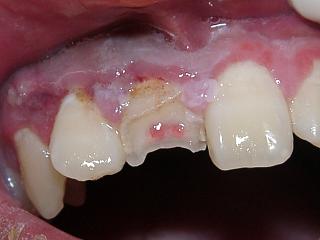

歯根破折 :象牙質、セメント質におよび歯髄に及ぶ破折 (図4)

歯根破折(図4)

歯牙の暫間的固定、または抜歯が必要になります。